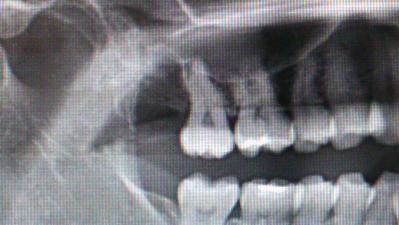

きょうは歯茎を切開し抜歯を行いました。

CTで確認していたので15分程で終わりました。

術後です。